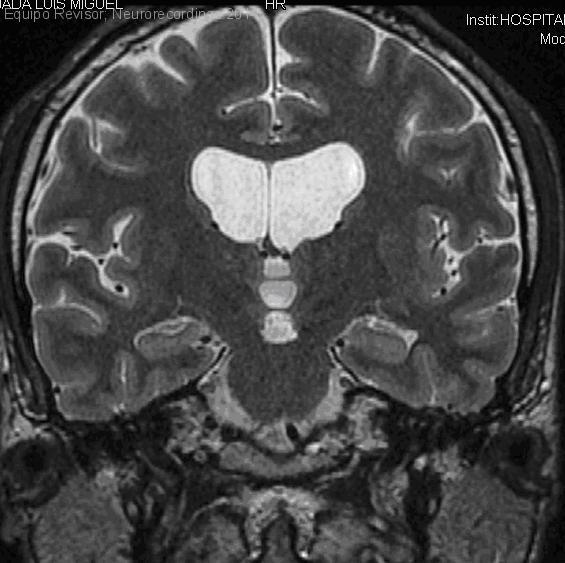

COMISURA ANTERIOR. ADHERENCIA INTERTALAMICA

Diagnóstico final: Comisura anterior. Adherencia intertalamica

Neurología: Anatomía. Variantes de la normalidad

Etiología: Anatomía. Variantes de la normalidad